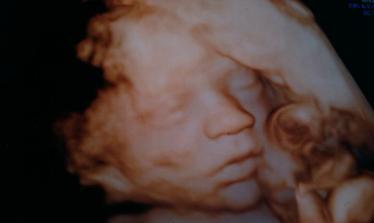

Liam-poslal nám ho anjel z neba

@xen21 veľmi kvalitné sono to bolo ale povedal aj pán doktor že je lepšie robiť takto fotočky lebo už je bábätko baculatejšie 🙂

Teším sa s tebou, že je Liamko úplne zdravučký.. zdravie je to najdôležitejšie, čo môže byť.. Liamko je kráááásny chlapček a ozaj podobnosť s Maxom je veľmi veľká, až neskutočné... úžasné... veľmi ti to prajem, budeš najlepšou maminkou pre svojho vytúženého drobčeka..šťastie sa začalo usmievať už aj na teba, čomu sa veľmi teším... zaslúžiš si to... tak želám pekný zvyšok tehotenstva a aj naďalej veľa veľa zdravíčka pre oboch..